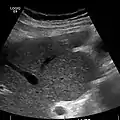

Ultrasound is routinely used in the evaluation of cirrhosis. It may show a small and nodular liver in advanced cirrhosis along with increased echogenicity with irregular appearing areas. Other liver findings suggestive of cirrhosis in imaging are an enlarged caudate lobe, widening of the fissures and enlargement of the spleen. An enlarged spleen, which normally measures less than 11–12 cm in adults, may suggest underlying portal hypertension. Ultrasound may also screen for hepatocellular carcinoma, and portal hypertension, by assessing flow in the hepatic vein. An increased portal vein pulsatility is an indicator of cirrhosis, but may also be caused by an increased right atrial pressure.[47] Portal vein pulsatility can be quantified by pulsatility indices (PI), where an index above a certain cutoff indicates pathology:

caudate lobe hypertrophy in ultrasound due to cirrhosis